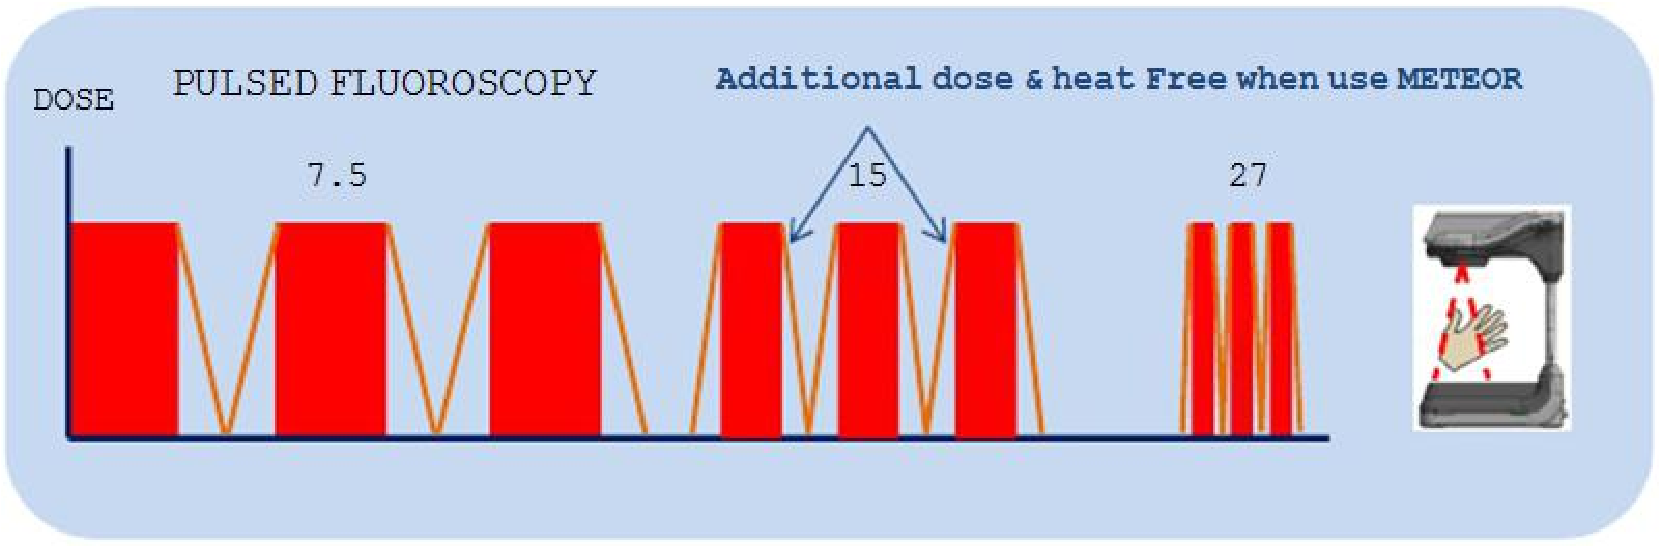

低剂量脉冲透视技术

基于“ALARA 辐射防护最优化”原则,CMN100 的设计理念追求放射性和 X 射线成像剂量达到相对合理平衡的状态。

低达 22.4W 的原装进口低功率 X 线发生装置及高转换效率的微像素平板探测器,提高设备安全稳定性能的同时,让临床享受到贴心的低剂量辐射安全;

高达 0.3mA 的低剂量脉冲透视工作模式,有效避免不必要的 X 射线溢出,最大限度的减少对使用者和被检对象的健康损害

帧数在 7.5FPS 到 27PFS 之间 & 有效脉宽控制在 30~100%之间

脉冲透视操作的总剂量比连续透视操作模式低 35~80%